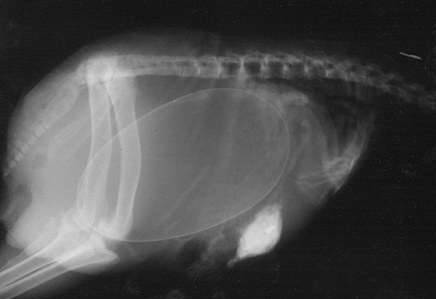

▼怀孕的狗狗